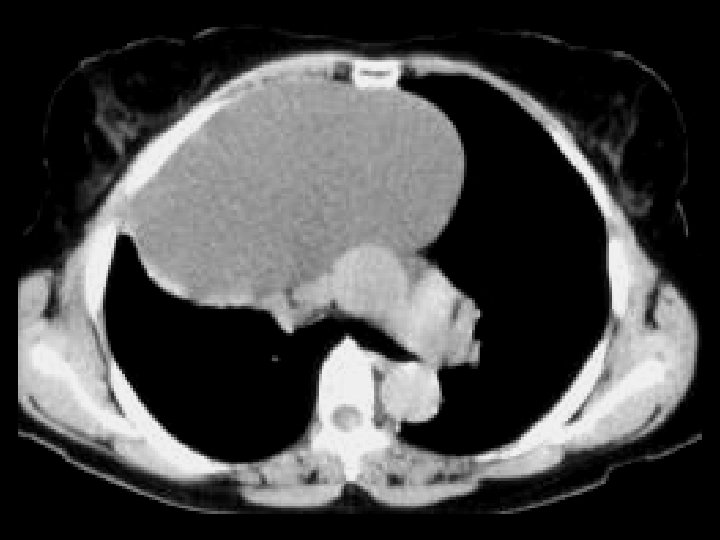

ADPKD • Findings: – Enlarged bilateral kidneys containing innumerable cysts – May also see hepatic cysts – Cysts complicated by hemorrhage or infection – NO increase risk of RCC • ddx: – NONE! – This is an Aunt Minnie!